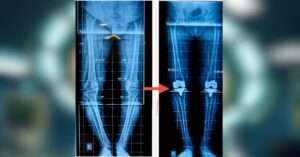

Your journey begins with a thorough evaluation. Dr. Shah will review your medical history, conduct physical examinations, and may order imaging tests like X-rays or MRIs to assess the extent of joint damage.

Using the robotic system, Dr. Shah will create a 3D model of your knee, allowing for precise planning. This step ensures that the implant is positioned correctly, optimizing alignment and function.

During the procedure, the robotic system assists Dr. Shah in removing damaged cartilage and bone, then guides the placement of the new knee implant. The system provides real-time feedback, ensuring accuracy throughout the surgery.